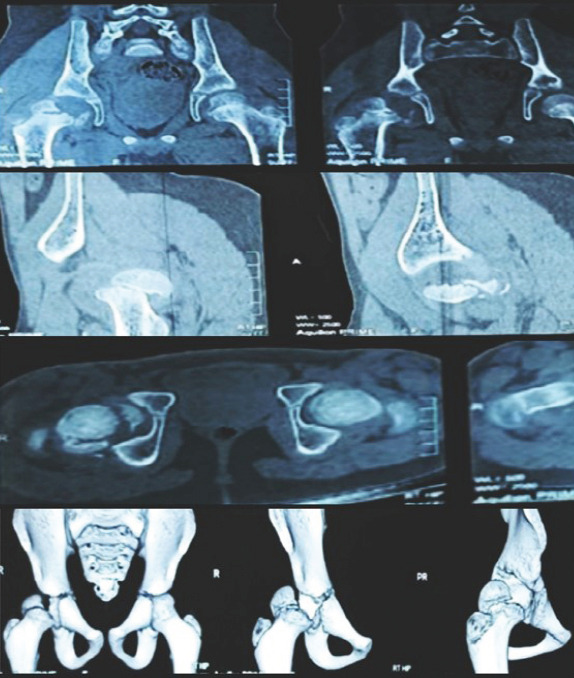

Case report: We present the case report with detailed history, examination, and treatment of a 12-year-old boy with an uncommon site of fracture at right transepiphyseal hip fracture with dislocation. Emergency initial operation was done and followed up for 2-year duration on regular basis. The patient has currently normal gait with painful terminally restricted movements.